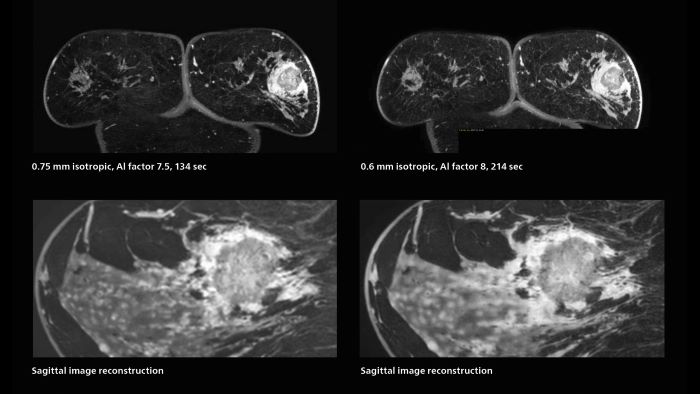

Fast, dynamic breast imaging for diagnostic confidence

Speed and high image quality are also important factors determining the diagnostic value of breast MRI. “When the spatial resolution is not high enough for making the diagnosis of breast cancer, a very difficult decision must be made,” says Dr. Katahira. “Since SmartSpeed now allows us to increase the resolution, we can often easily provide a confident answer. In the past with SENSE we used 1.2 mm isotropic voxels in breast imaging after contrast admission. With Compressed SENSE that is 0.8 mm. Now with SmartSpeed we can acquire 0.6 mm isotropic voxels and the images are so clear that even tiny details are clearly visible.” “For example, we can now scan 20 consecutive, very fast dynamic images of the mammary glands with a single 3-second volume acquisition. This allows us to see how the blood flow is progressing in a very different way.” “The use of SmartSpeed has considerably improved our breast cancer imaging, with higher temporal resolution, higher spatial resolution, and higher SNR compared to the past, when we were using just Compressed SENSE. In addition, the dynamic study is now more useful in diagnosis because the ultrafast dynamic scan can be taken every 3 seconds.”

3D MRI of breast cancer

Scanning was performed with two different voxel sizes. AI enabled volume MRI allows image reconstruction in other directions. Biopsy revealed invasive ductal carcinoma in this patient. Performed on Elition X.

The hospital’s routine ExamCards for breast imaging include: